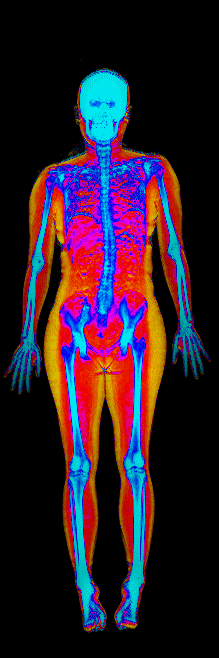

This page features real, anonymized DEXA scan images from BodyStats clients, organized by gender and body fat percentage in 5% increments. DEXA (Dual-Energy X-ray Absorptiometry) is the clinical gold standard for measuring body composition — far more accurate than scales, calipers, or visual estimates.

Each colorized scan shows the distribution of fat tissue (shown in warmer colors) and lean tissue (cooler colors) throughout the body. Compare your own DEXA scan to others in your range, or see what different body fat levels actually look like on a scan.

Female DEXA Scans by Body Fat %

15 to 20% body fat